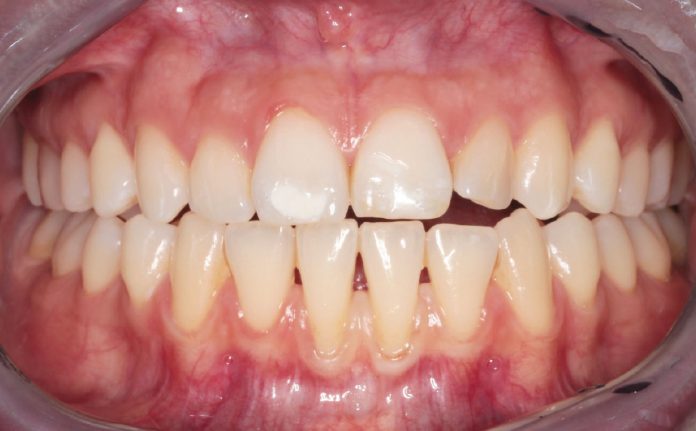

Il caso descritto riguarda una giovane paziente di 31 anni che si è presentata presso l’Unità Operativa di Odontostomatologia dell’Ospedale di Parma per recessioni gengivali di grado I di Miller della superficie vestibolare degli elementi 3.1 e 4.1. La paziente ha riferito deficit di coagulazione congenito e allergia alla mepivacaina.

All’esame obiettivo si è riscontrata scarsità della profondità del vastibolo in zona mandibolare anteriore. Si è deciso perciò di intervenire chirurgicamente eseguendo una vestibuloplastica inferiore con laser Nd:YAG.